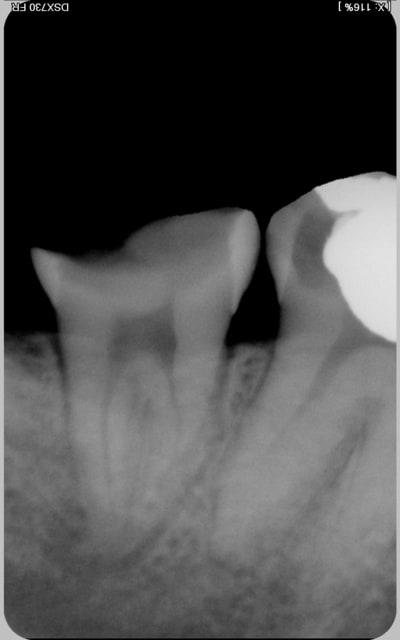

encore des radios,peut-etre assez moyen comme traitement...mais je vu pire...

les dernieres radios. patient en urgence ,abces... il voulait pas extraire la dent. j'ai lui bien explque et il a choisi de essayer de garder la dent. retrait,pas d'isolation avec la digue donc pas de tenon fibree,amalgam et screw post.traitement fait il ya 2 ans je crois.patient fidel de cabinet maintenent.

j'ai jamais utilise en roumanie l'amalgam et ca s'utilise pas du tout dans le cabinet du roumanie.